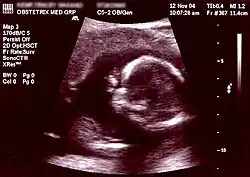

![]() Non-invasive prenatal test analysis | |

| Non-invasive | Ultrasound detection | Commonly dating scans (sometimes known as booking scans or dating ultrasounds) from 7 weeks to confirm pregnancy dates and look for multiple pregnancies. The specialised nuchal scan at 11–13 weeks may be used to identify higher risks of Downs syndrome. Later morphology scans, also called anatomy ultrasound, from 18 weeks may check for any abnormal development. Additional ultrasounds may be performed if there are any other problems with the pregnancy, or if the pregnancy is post-due. | First or second trimester |